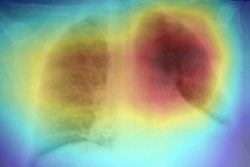

DarwinAI developed the COVID-19 program with the University of Waterloo to improve COVID-19 detection and risk stratification on chest radiography. In March, a Canadian team published research showing the COVID-Net deep convolutional neural network achieved promising early results, including 100% sensitivity, 80% positive predictive value, and 83% accuracy for identifying COVID-19 on a small test set of chest radiography studies.

Now, Red Hat and DarwinAI are gearing the tool up for clinical and research use with the help of underlying technology from a computational research group at the Boston Children's Hospital. The collaboration aims to make COVID-Net easier for clinicians to use, including through a web-based graphical user interface designed to work with Boston Children's open-source ChRIS framework.